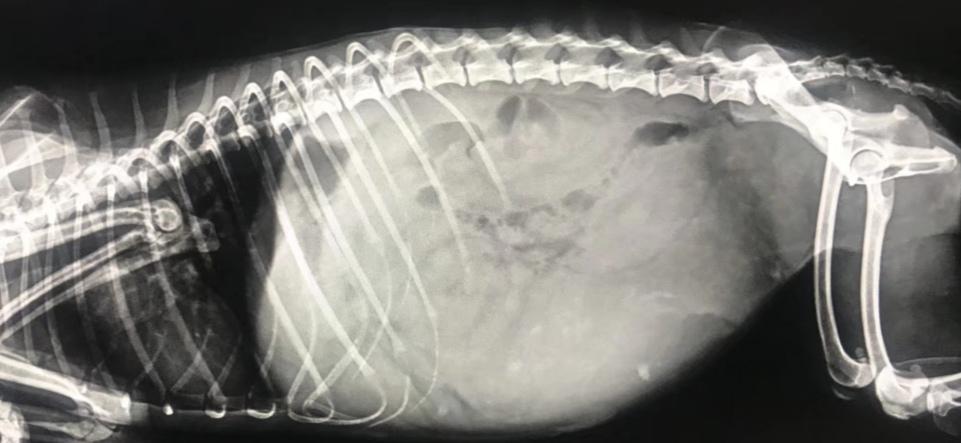

- X光显示腹部子宫膨大,里面有大量液体。

闭合性子宫蓄脓